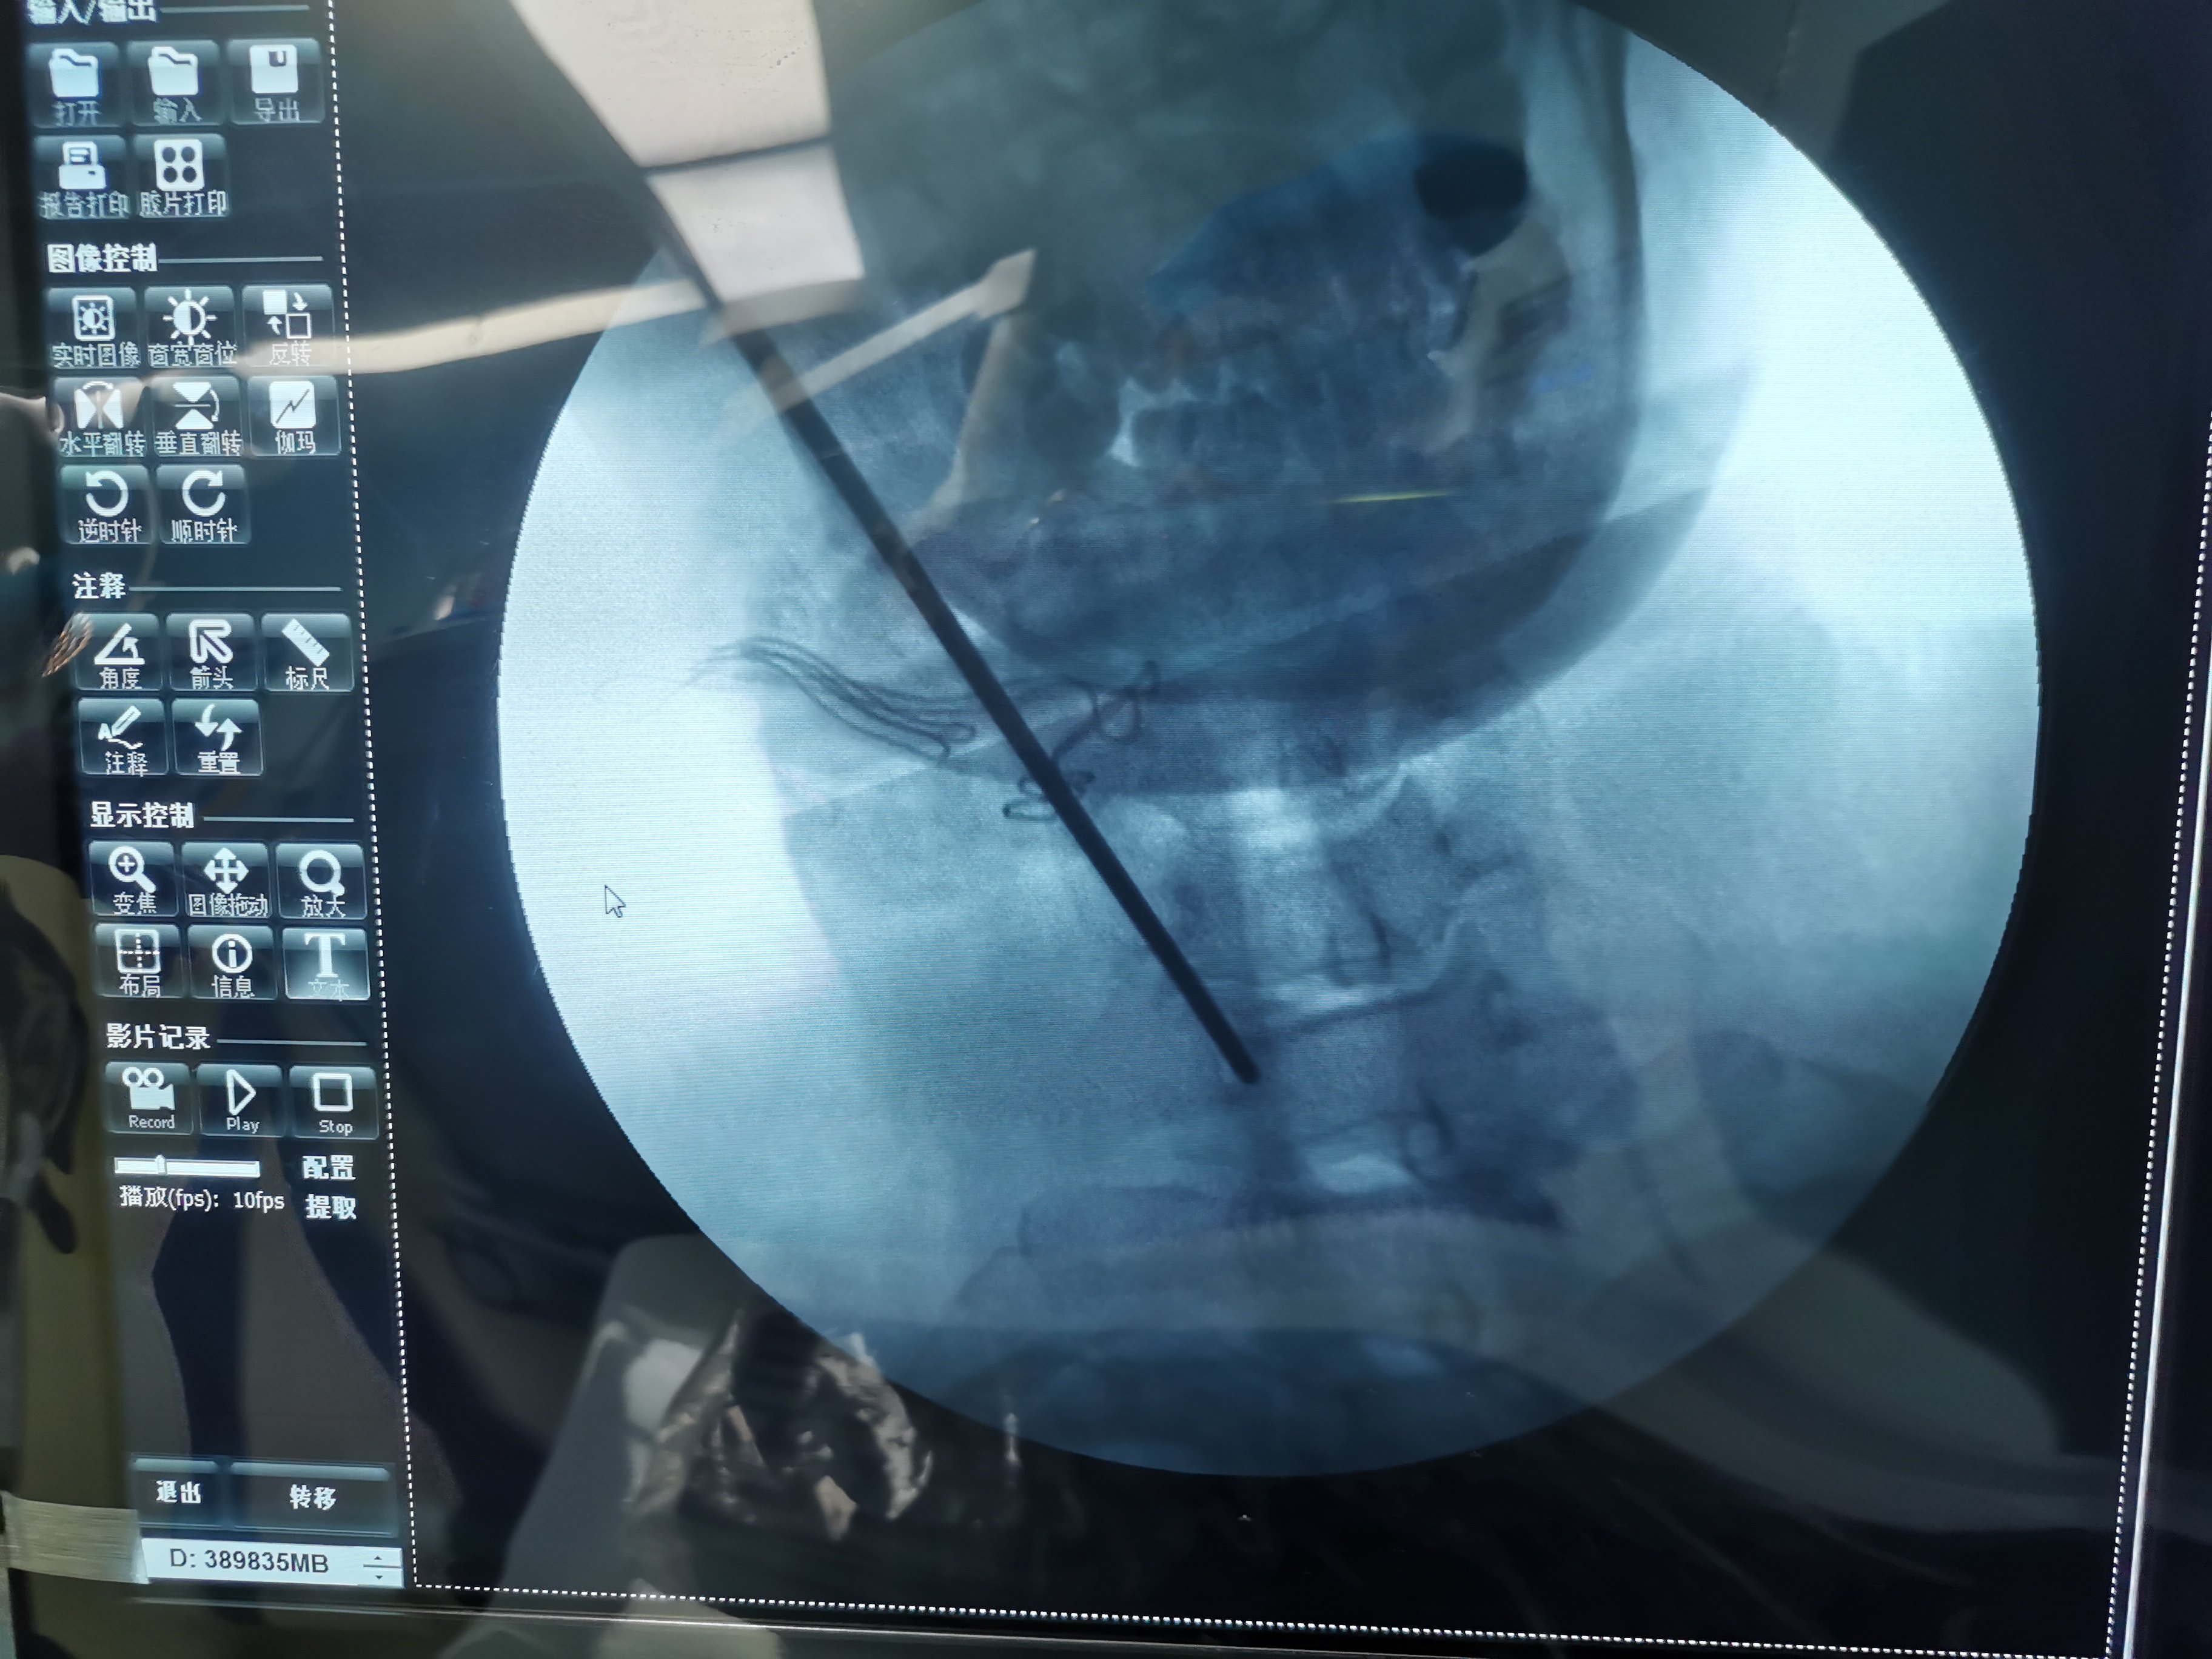

椎间孔镜(颈椎)

图片尺寸2667x2000